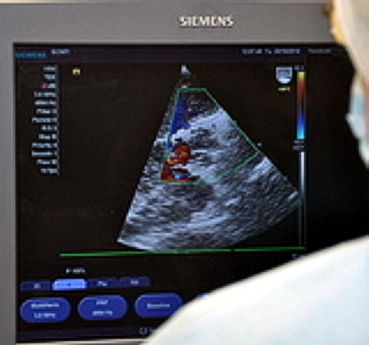

Первым пациентом, на котором была применена данная технология, стал 80-летний мужчина, поступивший в больницу с жалобами на ишемическую болезнь, одышку, потерю сознания и головокружения. В ходе обследования у пациента выявилось то самое критическое сужение аортального клапана. Кардиохирурги провели операцию с применением новой технологии. За процессом наблюдал врач сердечно-сосудистой хирургии из Екатеринбургской областной клинической больницы №1 Андрей Молчанов.

Контрольные исследования показали, что функции нового имплантированного клапана хорошие. По словам заведующего отделением сердечнососудистой хирургии БСМП Рамиса Якубова, до конца 2014 года запланировано провести еще две такие операции.